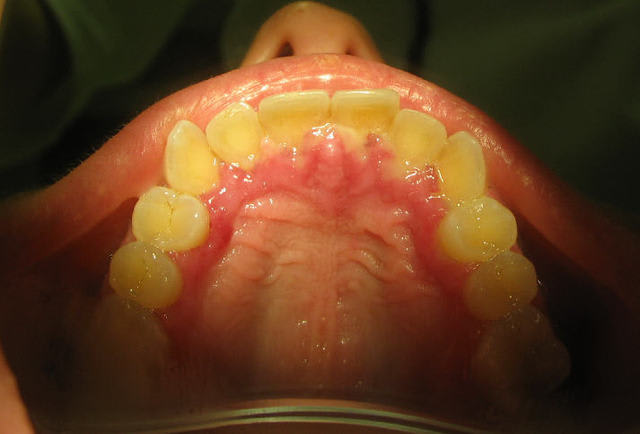

Je la vois aujourdh'hui (pour la première fois) en urgence et découvre ça (je l'ai pris en photo) et des aphtes sur les faces intérieures des joues et sur la langue, l'ensemble des gencives rouge luisant. Ce qu'on voit en gris ce n'est pas du pu mais de la gencive nécrosée.

Gingivite ulcéro-nécrotique ? bon !

Moi, je penserais plutôt peut-être à une primo-infection herpétique.

En voici une en photo ci-joint.